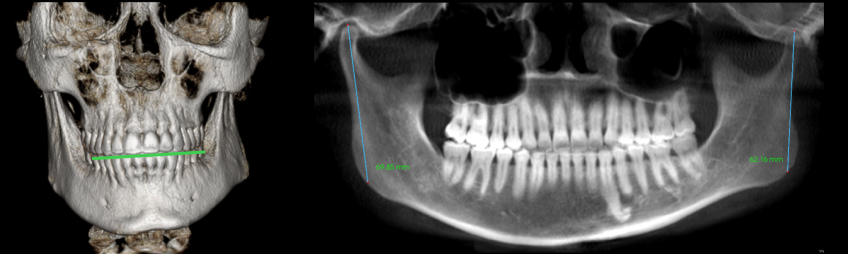

CBCT is ideal for evaluating osseous structures. The size and shape of the condyle and the intraarticular space can be assessed in conjunction with a comprehensive TM joint examination, providing insight into the position of the articular disk. In both adults and growing individuals, the condyle should take up about 66% of the glenoid fossa. If the condyle is not proportionate to the glenoid fossa, it may indicate an early growth disturbance, condylar breakdown, or a combination of both.

In addition to the size of the condyle, a normal shape of the condyle indicates protection for the articular disk, signifying that the articular cartilage is safeguarded. However, when there’s a disruption of the articular cartilage or the growth center, it results in a loss of vertical dimension in the mandibular condyle, leading to shorter ramus lengths.

The height from the top of the condyle to the angle of the ramus (gonion) in adult patients is 60–70 mm. For a 5-year-old patient, the expected height is 40 mm, with 2–3 mm of growth annually. An adult patient with values below these ranges suggests arrested development. In growing patients, measurements below average indicate herniation of the articular disk.”

Differences in condylar heights often influence the maxillary arch, leading to an occlusal cant or a stepped occlusal plane (Fig. 5).